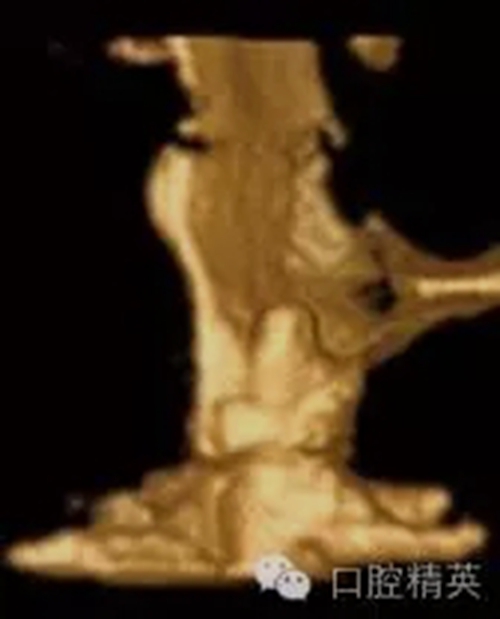

圖1c:術后用ICATCBCT進行三維立體效果再現(xiàn),顯示種植體穿入上頜竇的實踐情況

圖5c:CBCT三維立體效果再現(xiàn)顯示了25號牙處嚴重的頰側骨板裂開。